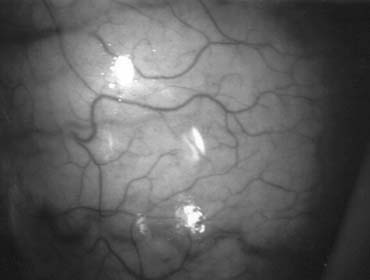

Microsurgical Testicular Sperm Extraction

Testicular sperm extraction can result in injury to the testicular blood supply and lead to subsequent atrophy.70 The use of an operating microscope for standard open diagnostic testes biopsy allows identification of an area in the tunica albuginea free of blood vessels (Fig. 37), minimizing the risk of injury to testicular blood supply and allowing a relatively blood-free biopsy specimen.16 Using the microscope for testis biopsy, Schlegel15 discovered that in men with nonobstructive azoospermia, some of the tubules were larger than others. The larger tubules are more likely to yield sperm. Previous studies71 revealed that testicular biopsy in men with nonobstructive azoospermia display considerable heterogeneity. Examination of permanently fixed biopsy specimens that display heterogeneity reveal that tubules with spermatogenesis are of considerably larger diameter than tubules that are Sertoli cell-only (Figs. 38 and 39). This difference can be readably observed under the operating microscope.

Fig. 37. Microsurgical techniques allow clear identification of blood vessels on the tunica albuginia of the testis.

Fig. 38. Tubules with spermatogenesis are of larger diameter than tubules with Sertoli cell-only pattern.

Fig. 39. Selective removal of large seminiferous tubules with microsurgical testicular sperm extraction. A significantly smaller quantity of tissue is taken compared with conventional nonmicrosurgical testicular sperm extraction.